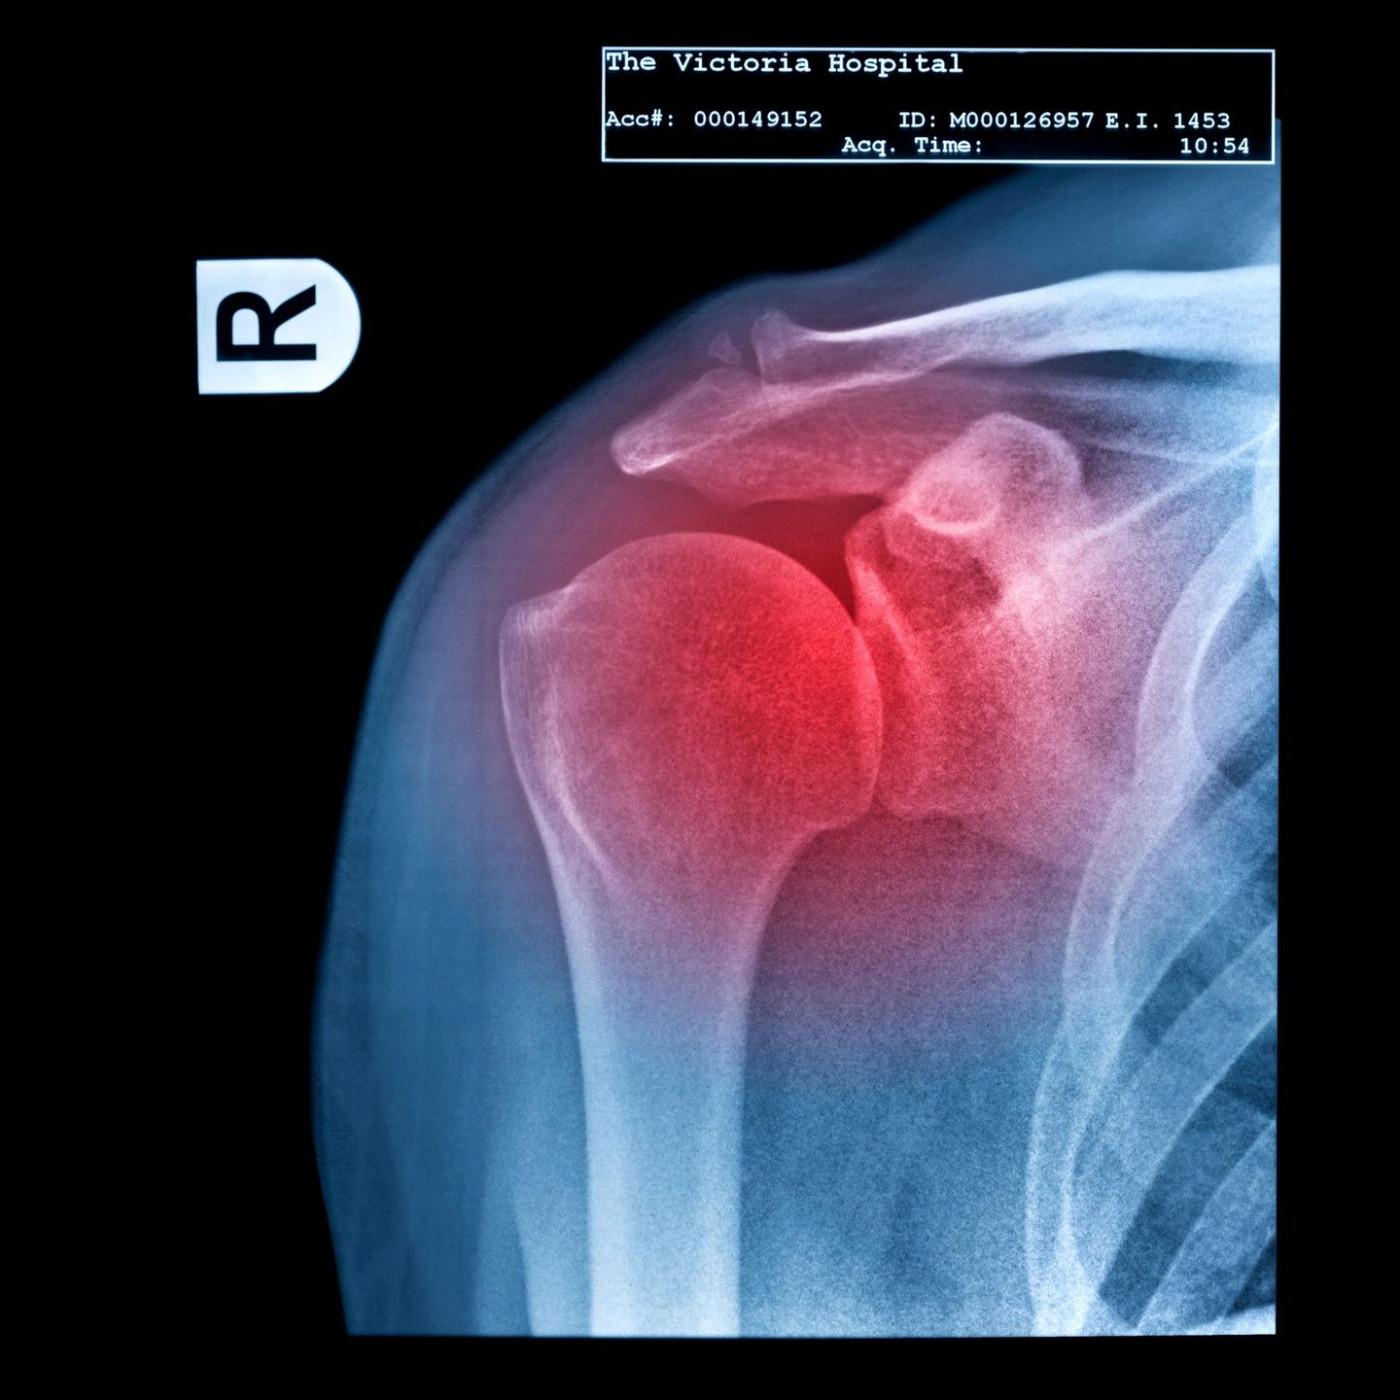

• Osteoporose

• Knochen